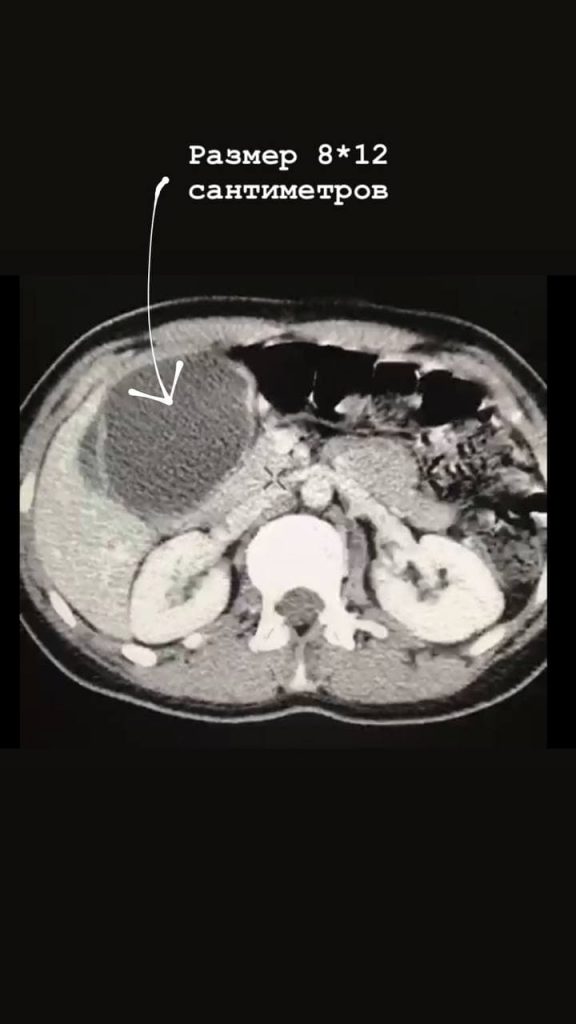

В Раменскую больницу поступила женщина с жалобами на резкие боли в животе. В результате проведенной диагностики у пациентки выявили эхинококковую кисту размером 8х12 см, занимающую всю левую долю печени.

«Хирургами была выполнена сложнейшая операция по удалению эхинококковой кисты, при этом удалось сохранить всю левую долю печени. В ходе удаления новообразования, крайне важно не повредить оболочку кисты, тем самым, не дать выход ее содержимому, которое за считаные минуты обсеменяет орган, вызывая мощнейшую интоксикацию, ведущую к смерти в течение 1-2х часов. Тем не менее, и жить с эхинококкозом крайне опасно. Киста непрерывно растет в размерах, сдавливая ближайшие сосуды и препятствуя нормальному кровотоку в органе», — рассказал кандидат медицинских наук, заместитель главного врача Раменской больницы по хирургической помощи Дмитрий Зинатулин.